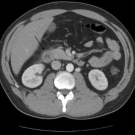

A 23-year-old white man presented to the emergency department with nonradiating epigastric abdominal pain accompanied by nausea and vomiting for 2 to 3 days.

04/26/2022